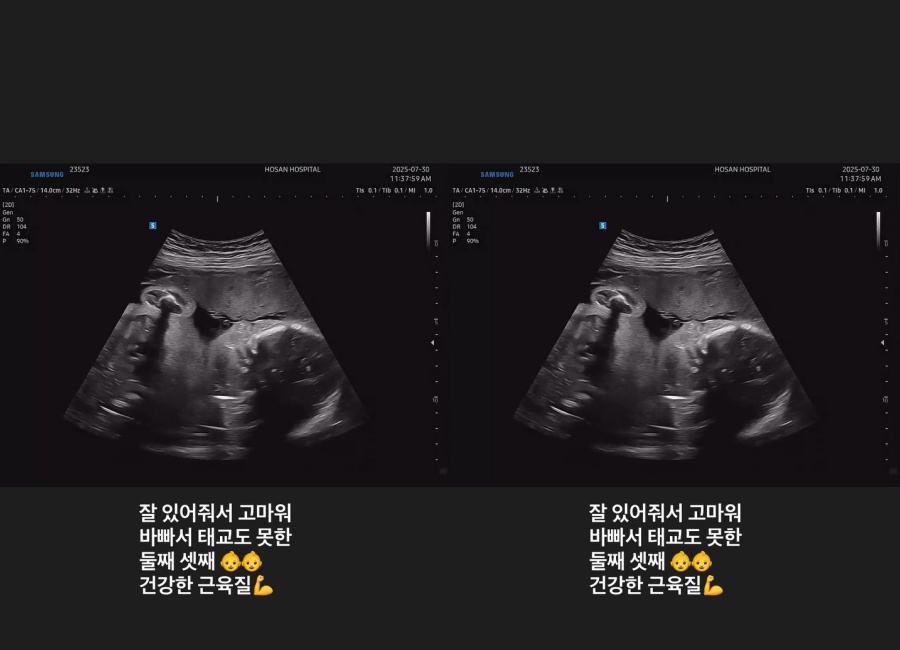

続いて、エコー検査を終えたとみられるチ・ソヨンは「元気でいてくれてありがとう」「忙しくて胎教もできない2人目、3人目、元気な筋肉質」と書き込み、すくすく育っている胎児の様子も公開した。